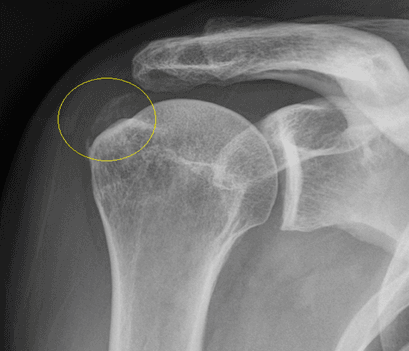

Aspect radiologic depozit calcaros tendon supraspinos

3. Calcificare masivă tendon supraspinos – imagine radiologică